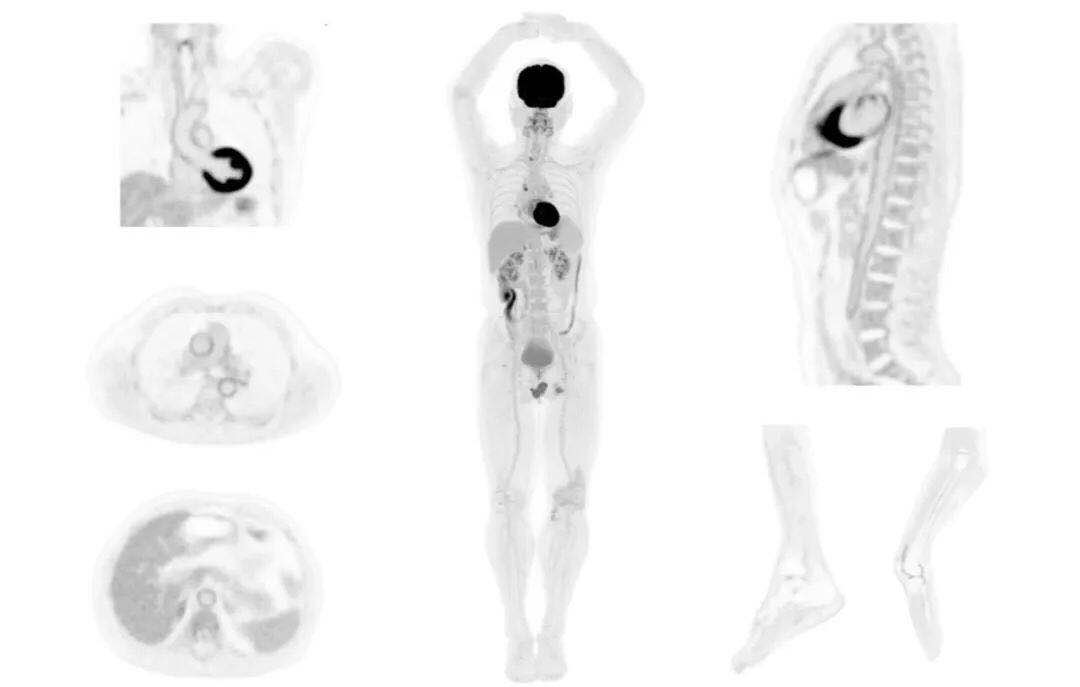

肺癌轉(zhuǎn)移及復(fù)發(fā)

患者男性,66歲,七年前發(fā)現(xiàn)右肺肺癌,其間手術(shù)兩次,共切除兩個(gè)肺葉,復(fù)查;

診斷意見,回腸轉(zhuǎn)移,右肺殘留部復(fù)發(fā)